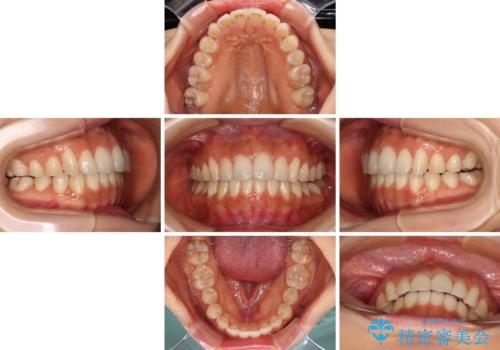

カリエールディスタライザーを併用したことで、確実かつ短期間で治療を終えることができました。